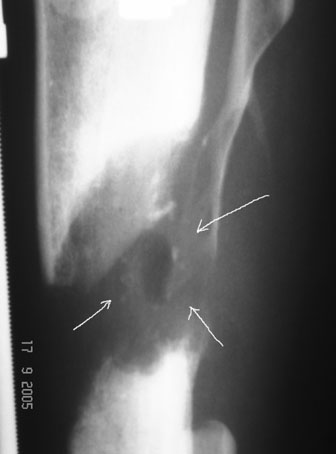

С места аварии в районную больницу, где произвели ампутацию правой голени. Дальше в клинику спец. помощи, где на левой голени были удалены нежизнеспосбные инфицированные отломки, (дефект 13 см) и наложен аппарат Гофмана. Детали неизвестны. Со слов больного, инфекционный процесс левой голени купирован не был. В феврале аппарат был снят и произведен остеосинтез гвоздем (before1;2). В мае, объективно: В нижней трети голени функционирует свищ, отделяемое гнойное: золотистый стафилокок, чувствительный к большинству антибиотиков.

Ввиду относительной тугоподвижности ложного сустава и наличия признаков репаративной активности костной ткани рентгенологически, после 10 дней компрессии на стыке отломков, начали дистракцию по 1мм в день. Выписан на амбулаторное лечение. Отделяемое в нижней трети голени прекратилось, ранка закрылась. Интраоперационно и 5 дней после операции получал ципроксациллин. В июле по передней поверхности голени в зоне регенерата открылась ранка с обильным гнойным отделяемым. После локального лечения, ранка в течении двух недель эпителизировалась и полностью закрылась. Дистракцию не прекращали. (during 1, 2)

10 дней назад ранка на передней поверхности средней трети голени и по внутренней поверхности нижней трети голени, (по проекции стержня апп. Гофмана) открылись вновь. В настоящий момент отделяемого из обеих ран нет (wound1;2).

Рентгенологически определяется дистракционный регенерат удовлетворительной плотности и наличие в нем полости (now 1;2;3).